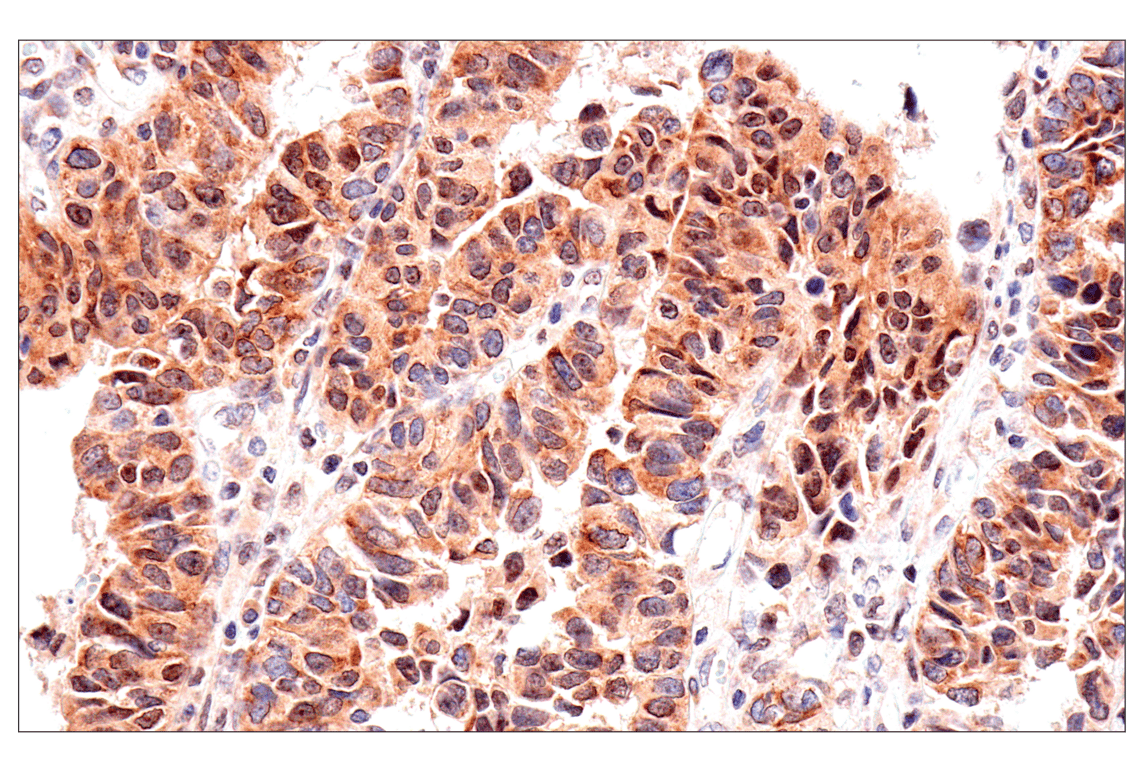

Immunohistochemical analysis of paraffin-embedded human hepatocellular carcinoma using ADAR1 p150 Isoform (E6U1U) Rabbit mAb.

Immunohistochemistry Image 3: ADAR1 p150 Isoform (E6U1U) Rabbit Monoclonal Antibody